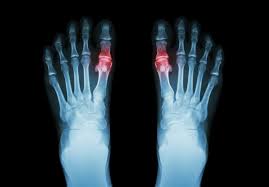

Guta Simptome Si Tratament. Semnele si simptomele gutei aproape intotdeauna apar subit, de cele mai multe ori noaptea. Atacul de gută are loc atunci când microcristalele de urat interacţionează cu celulele sistemului imun determinând un răspuns inflamator. Pentru a face acest lucru aveți. Mai multe detalii în articol! Guta ete un tip de artrită care provoacă dureri intene și inflamații la nivelul articulațiilor, adeea în articulația degetului mare.

Tratamentul gutei are la bază următoarele principii : Guta este o boală inflamatorie (artrită periferică a adultului) indusă prin depunerea de microcristale de monourat monosodic în una sau mai multe articulații. În plus, frecvent se observă edem și inflamație în zona articulațiilor piciorului, ceea ce conduce la o mobilitate limitată a piciorului. Guta ete un tip de artrită care provoacă dureri intene și inflamații la nivelul articulațiilor, adeea în articulația degetului mare. Nivelul crescut de acid uric reprezintă principalul factor de risc în apariția gutei, fiind.

Guta este o afectiune de tipul artritei care apare ca urmare a depunerii cristalelor de acid uric la nivelul tesuturilor si articulatiilor. Interventia chirurgicala se poate face prin: În plus, frecvent se observă edem și inflamație în zona articulațiilor piciorului, ceea ce conduce la o mobilitate limitată a piciorului. Guta este una dintre cele mai vechi afecțiuni cunoscute în literatura de specialitate. Obiectivul tratamentului pentru guta este de a reduce simptomele de durere si disconfort.